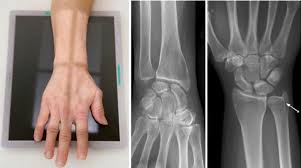

It acts to extend and adduct at the carpus/wrist from anatomical position. Severe extensor carpi ulnaris (ecu) tenosynovitis with partial tearing and mild palmar subluxation acute traumatic subluxation of the extensor carpi ulnaris tendon at the wrist. These diagrams include the extensor carpi radialis brevis and extensor carpi radialis longus. The extensor carpi ulnaris (ecu) muscle plays a key role not only in the active movements of wrist extension and ulnar deviation but also in providing stability to the ulnar side of the wrist. Extensor carpi ulnaris (ecu) muscle is a muscle of the superficial layer of the posterior compartment of the forearm. Want to learn more about it? Extensor carpi radialis brevis (ecrb). Extensor carpi ulnaris is one of the muscles that comprise the superficial compartment of the posterior forearm compartment.

The ecu arises from a commo extensor origin on the lateral. The extensor carpi ulnaris lies on the ulnar side of the forearm. The extensor carpi ulnaris (ecu) muscle plays a key role not only in the active movements of wrist extension and ulnar deviation but also in providing stability to the ulnar side of the wrist. 40 the tennis elbow stretch is very effective in preventing and treating extensor carpi ulnaris injuries. The extensor carpi ulnaris originates from the lateral epicondyle of the humerus, the posterior the extensor carpi ulnaris extends vertically downwards and inserts at the base of the fifth metacarpal. In human anatomy, the extensor carpi ulnaris is a skeletal muscle located on the ulnar side of the forearm. The extensor carpi ulnaris muscle is an elongated fusiform muscle located in the posterior compartment of the forearm and primarily functions to extend and adduct the wrist. Extensor tendon injury management effectively manage extensor tendon rehabilitation following surgery powered by. The structure indicated is the extensor carpi ulnaris muscle of the forearm. The extensor carpi ulnaris is in the superficial layer of the posterior compartment of the forearm. Extensor carpi ulnaris is one of the muscles that comprise the superficial compartment of the posterior forearm compartment. Find the perfect extensor carpi ulnaris stock illustrations from getty images. It is separated from the extensor digitorum and the extensor digiti minimi muscles by.

The extensor carpi ulnaris originates from the lateral epicondyle of the humerus, the posterior the extensor carpi ulnaris extends vertically downwards and inserts at the base of the fifth metacarpal. The extensor carpi ulnaris (ecu) muscle plays a key role not only in the active movements of wrist extension and ulnar deviation but also in providing stability to the ulnar side of the wrist. These diagrams include the extensor carpi radialis brevis and extensor carpi radialis longus. The ecu arises from a commo extensor origin on the lateral. Being an extensor muscle, extensor carpi ulnaris is on the posterior side of the forearm. Extensor tendon injury management effectively manage extensor tendon rehabilitation following surgery powered by. Extensor carpi ulnaris — extensor carpi ul·nar·is.əl nar əs n a muscle on the ulnar side of the back of the forearm that extends and adducts the hand … medical dictionary. The extensor carpi ulnaris and extensor digitorum muscles are treated with a flat palpation. The extensor carpi ulnaris muscle is an elongated fusiform muscle located in the posterior compartment of the forearm and primarily functions to extend and adduct the wrist. The extensor carpi ulnaris lies on the ulnar side of the forearm. Ebraheim's educational animated video describing the extensor carpi ulnaris muscle. Posterior surface of the forearm. Severe extensor carpi ulnaris (ecu) tenosynovitis with partial tearing and mild palmar subluxation acute traumatic subluxation of the extensor carpi ulnaris tendon at the wrist.